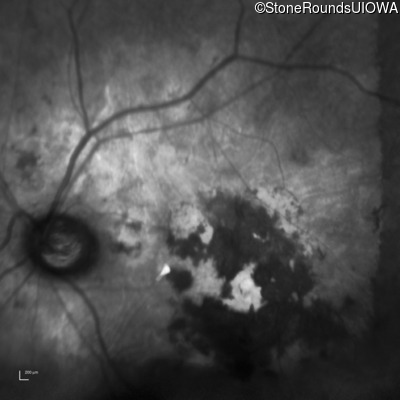

Infrared Fundus Photograph - Left - Count Fingers 2'

Exemplar